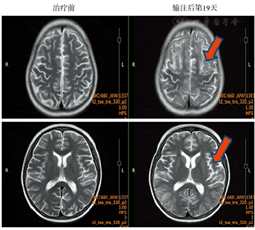

患者,女,12岁,2016年11月17日在外院诊断为B-ALL,当时融合基因筛查示E2A-PBX阳性,染色体核型分析示der(19),t(1;19)(q23; p13)。给予PVLD方案诱导治疗后取得完全缓解,之后予以CAM、PVLD及大剂量甲氨蝶呤(MTX)等方案化疗4个疗程。2017年6月5日患者疾病复发,2017年8月1日转至我科行CAR-T细胞治疗。2017年8月5日在患者父母签署知情同意书后,采取患者外周血60 ml用于制备CAR-T细胞,在等待CAR-T细胞回输期间,患者出现反复高热、齿龈疼痛及全身骨痛,外周血幼稚细胞增多,考虑疾病进展,给予VMP(长春地辛+米托蒽醌+甲泼尼龙)方案化疗控制肿瘤负荷,患者于9月18日出现2次癫痫发作(部分性发作),脑脊液常规生化检查及影像学检查未发现异常,予以卡马西平口服预防治疗。9月20日复查骨髓示原始淋巴细胞占0.940,血常规示HGB 71 g/L, PLT 16×109/L, WBC 6.4×109/L,中性粒细胞2.8×109/L,淋巴细胞0.8×109/L,幼稚细胞占0.38。血清细胞因子检测示IL-6 11.8 pg/ml(正常参考值<5.9 pg/ml),IL-2受体1 119 U/ml(正常参考值223~710 U/ml),TNF-α 6.3 pg/ml(正常参考值<8.1 pg/ml)。9月21日起予以FA(氟达拉滨25 mg/m2+阿糖胞苷1 g/m2)方案预处理化疗3 d,9月27日(第0天)起行患者自体CAR-T细胞输注,输注CAR-T细胞总量为0.3×106/kg,分2 d输注(第0天输注CAR-T细胞总量的30%,第1天输注细胞总量的70%)。患者于10月4日(第7天)开始出现发热且体温逐渐增高,血清细胞因子检测示IL-6 13.6 pg/ml,IL-2受体1 415 U/ml,TNF-α 11 pg/ml。10月5日(第8天)患者呈持续高热,体温最高达41.3 ℃,给予对乙酰氨基酚口服及物理降温等措施均退热效果不佳,予以托珠单抗(8 mg/kg)静脉滴注治疗后体温在2 h后明显下降,一度恢复至正常,次日起患者又出现发热,体温逐渐升高,10月7日(第10天)体温最高达39.9 ℃。10月8日(第11天)起患者出现胸闷、气急等不适,伴阵发性呛咳,指末氧饱和度下降至85%~92%,胸部CT示两肺多发渗出性改变(图1);血气分析提示低氧血症,血常规示HGB 67 g/L,PLT 17×109/L,WBC 1.18×109/L,中性粒细胞0.2×109/L,幼稚细胞占0.02;生化检查示总胆红素(TBIL)17.5 μmol/L(正常参考值5.1~20.5 µmol/L),ALT 199 U/L(正常参考值7~40 U/L),AST 949 U/L(正常参考值13~35 U/L),LDH 17 060 U/L(正常参考值120~250 U/L),尿酸539 μmol/L(正常参考值155~357 μmol/L);血清细胞因子检测示IL-6>1 000 pg/ml,IL-2受体2 985 U/ml。予以面罩吸氧(5 L/min),积极抗感染、保肝,水化、碱化和利尿治疗,并第二次使用托珠单抗(8 mg/kg)治疗。10月9日(第12天)患者体温恢复正常,但胸闷、气急症状无缓解,出现皮肤多处大片瘀斑,出凝血常规示凝血酶时间(TT)54.5 s(正常参考值14~21 s),APTT 37.5 s(正常参考值25.0~36.2 s),纤维蛋白原1.82 g/L(正常参考值2.00~4.50 g/L),D-二聚体37.03 mg/L(正常参考值<0.55 mg/L),纤维蛋白降解产物(FDP)112.2 g/L(正常参考值2.0~4.5 g/L);生化检查示TBIL 48.6 µmol/L,ALT 250 U/L,AST 1 102 U/L,LDH 18 561 U/L。患者肝功能损害及凝血功能障碍加重,加强保肝和输注血浆、血小板等支持治疗;予以甲泼尼龙(40 mg每12 h 1次)静脉滴注,BiPAP呼吸机辅助通气。之后患者皮肤出血倾向改善,胸闷气急症状好转,氧需求量逐渐减少。10月12日(第15天)复查血常规示外周血幼稚细胞消失,出凝血常规示APTT 20 s,TT 30.2 s,D-二聚体11. 31 mg/L,FDP 53.2 g/L,肝功能检查示TBIL 35.1 µmol/L,ALT 117 U/L,AST 329 U/L,均较前好转,停止BiPAP呼吸机使用。10月14日(第17天)下午起患者突然出现四肢抽搐伴双眼凝视,每次持续5~10 min,之后反复发作,发作间期意识不清,考虑为癫痫持续状态。脑电图显示背景活动见α节律,间有θ波及少量低波幅β波,双侧额颞顶部偶见尖慢波发放,支持大脑皮层的广泛损害表现。予以地西泮(微泵静注5 mg/h)抗癫痫,甘露醇脱水,激素改为地塞米松(10 mg每6 h 1次)静脉滴注治疗,2 d后患者意识恢复正常,无癫痫发作,予以口服丙戊酸钠维持治疗,此时检查头部MRI可见两侧大脑皮层散在片状异常信号影(图2);激素逐渐减量至10月19日(第22天)停用。10月25日(第28天)血常规示HGB 95 g/L,PLT 13×109/L,WBC 1.06×109/L,中性粒细胞0.2×109/L,无幼稚细胞;C反应蛋白(CRP)0.1 mg/L;肝肾功能、出凝血常规及D-二聚体、FDP均正常;血清细胞因子IL-6 199 pg/ml,IL-2受体1 463 U/ml,TNF-α 19.1 pg/ml。10月30日(第33天)好转出院。

治疗前患者头部MRI未见明显异常;输注后第19天可见两侧大脑皮层散在片状异常信号影